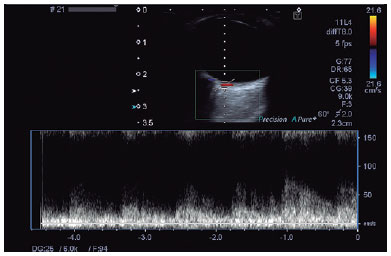

We scheduled orbital CDUS examinations for patients included in the study and receiving CS treatment and for the healthy volunteers. We performed all posterior ciliary artery (PCA)-oriented analyzes using a Toshiba Aplio 500 with a 6 MHz high-frequency linear array transducer. We examined the patient group using CDUS immediately before and after the treatment. The same radiologist examined all participants (in the supine position with their eyes closed) using the same device. All Doppler imaging procedures were performed between 11.00 am and 13.00 pm to avoid diurnal variations in ocular blood flow. The radiologist applied conductive gel on the closed eyelids and was careful not to apply too much pressure on the globe. Horizontal and vertical gray-scale scanning images of the orbit helped exclude possible pathologies. The radiologist localized the PCAs considering the orbital anatomy and measured the blood flow velocities by setting the appropriate marker angles to the vessel tract. The radiologist also measured and recorded peak systolic velocity (PSV), end-diastolic velocity (EDV), and resistivity index (RI) values (Figure 1).

10-fig01.jpg)